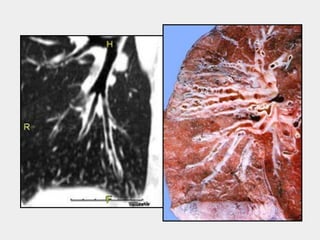

TC de tórax

§ Padrão ouro

§ Definição tomográfica

§ Anel de sinete

§ Não redução gradual do brônquio

§ Brônquio visualizável a 1 cm da pleura

TC de tórax §Padrão ouro § Definição tomográfica § Anel de sinete § Não redução gradual do brônquio § Brônquio visualizável a 1 cm da pleura